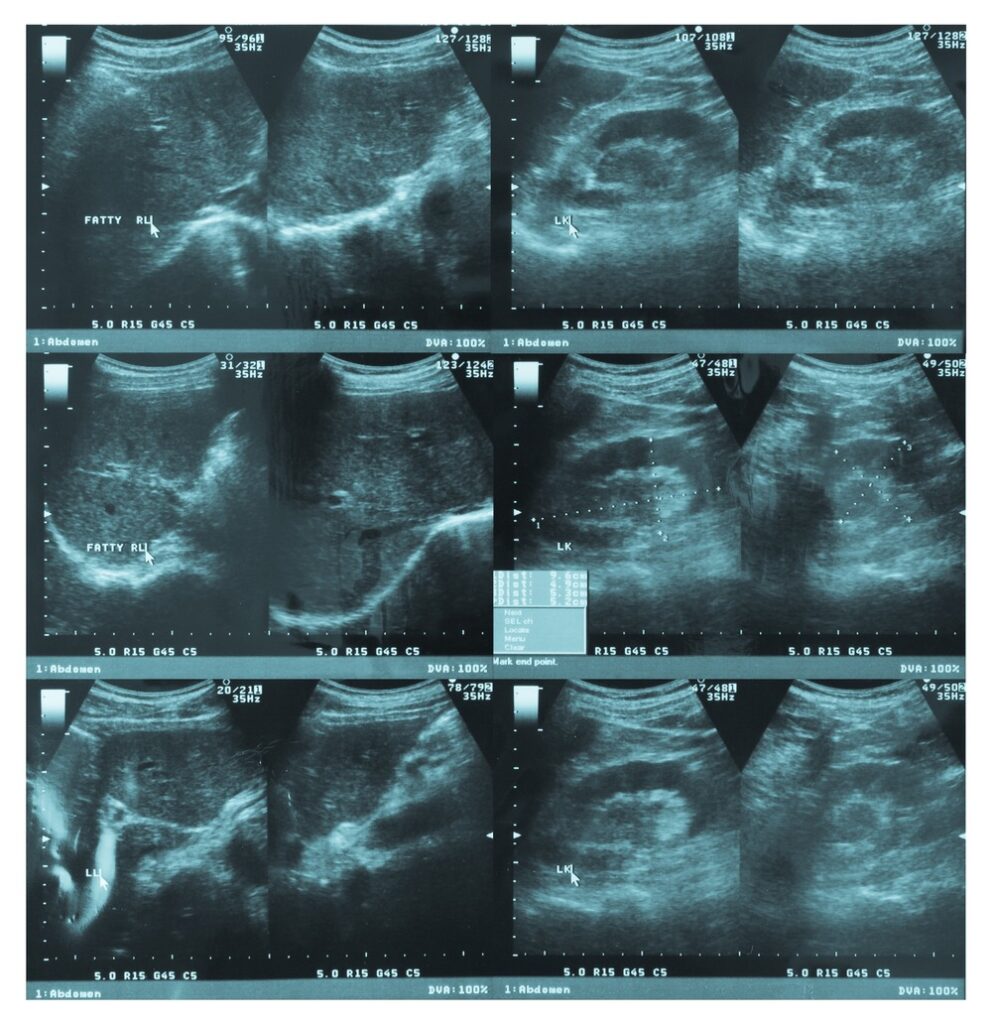

Abdomen (tummy/belly), Urinary tract ultrasound (Kidney, ureter and bladder) and Testes is a non-invasive medical imaging to check the organs and structures inside your abdominal cavity. This includes liver, gallbladder, pancreas, bile duct, spleen, kidneys, upper and lower part of the ureter (a tube which drains the urine from the kidney to the bladder), bladder, prostate, seminal vesicles, both testes and surrounding tissues.

Abdomen (tummy/belly), Urinary tract ultrasound ((Kidney, ureter, and bladder) and Testes is a non-invasive medical imaging to check the organs and structures inside your abdominal cavity. This includes liver, gallbladder, pancreas, bile duct, spleen, kidneys, upper and lower part of the ureter (a tube which drains the urine from the kidney to bladder), bladder, prostate, seminal vesicles, both testes and surrounding tissues.

Abdomen, Urinary tract, and Testes ultrasound can be used to check for a combination of variety of conditions such as:

You will be asked to lie down on the scan couch(bed) comfortably. Our well qualified experienced specialist ultrasound Practitioner/Sonographer or Consultant Radiologist will put water-based gel on your whole belly and scrotum. Thereafter, they examine all included organs by placing the probe (camera) over the gel on your whole belly and scrotum.